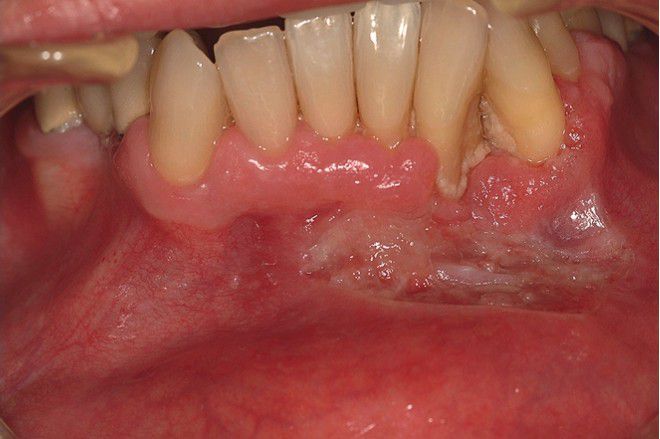

Histoplasmosis

. This ulcerated granular lesion involves the mandibular labial vestibule and is easily mistaken clinically for carcinoma. Biopsy established the diagnosis.